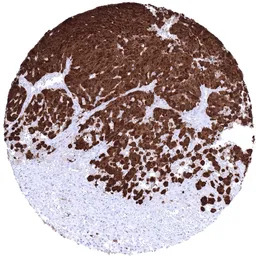

IHC-P analysis of human skin Malignant melanoma tissue section using GTX04404 S100 antibody [MSVA-490R] HistoMAX.

Skin Malignant melanoma with strong S100 beta positivity in all tumor cells.